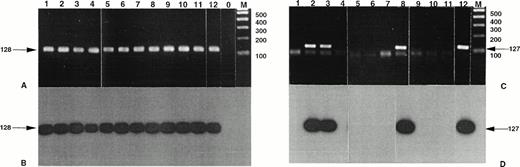

Standard PCR of the RT-PCR assay allowed the detection of NPM-ALK transcripts in 2 of the 15 CD30+ primary CTCL (cases no. 8 and 10) and in 3 of the 11 CD30+ secondary cutaneous lymphoma (cases no. 1, 2, and 3; Fig 2 and data not shown). Furthermore, the nested PCR allowed the detection of the NPM-ALK transcript in 1 of the 11 LyP (case no. 4); in 7 (cases no. 5 through 11) of the 15 CD30+ primary CTCL, including the above-mentioned 2 cases; and in the 3 previously detected cases of the 11 CD30+ secondary cutaneous lymphomas. After ethidium bromide staining showing the same sized amplicons, these results were confirmed both by direct sequencing and by Southern blot hybridization with the junction-specific oligoprobe NPM-ALK-J. The study of MF and BID samples did not show any NPM-ALK transcript after the standard PCR of the RT-PCR assay. However, nested amplification showed NPM-ALK specific amplicons in 6 of the 27 MF and in 1 eczema of the 16 BID samples (data not shown).

Detection of NPM-ALK and reciprocal ALK-NPM transcripts by nested RT-PCR. Total RNA was extracted from frozen skin biopsies or cultured cells and submitted to nested RT-PCR analysis, followed by electrophoresis on 2% agarose gel. Lanes 1, 2 and 3, cases no. 1, 2, and 3, respectively, CD30+ secondary CLCL; lane 4, case no. 4, LyP; lanes 5 through 11, cases no. 5 through 11, CD30+ primary CLCL; lane 12, t(2;5)+SU-DHL-1 cell line; lane 0, no template; lane M, molecular weight marker 100-bp DNA ladder (GIBCO-BRL). Detection of NPM-ALK transcripts: (A) ethidium bromide staining and (B) radioautography. Detection of ALK-NPM transcripts: (C) ethidium bromide staining and (D) radioautography. The gels were transferred to a nylon membrane, hybridized either with the NPM-ALK-J probe (B) or the ALK-NPM-J probe (D), and radioautographed. Sizes are indicated in bases.

Detection of NPM-ALK and reciprocal ALK-NPM transcripts by nested RT-PCR. Total RNA was extracted from frozen skin biopsies or cultured cells and submitted to nested RT-PCR analysis, followed by electrophoresis on 2% agarose gel. Lanes 1, 2 and 3, cases no. 1, 2, and 3, respectively, CD30+ secondary CLCL; lane 4, case no. 4, LyP; lanes 5 through 11, cases no. 5 through 11, CD30+ primary CLCL; lane 12, t(2;5)+SU-DHL-1 cell line; lane 0, no template; lane M, molecular weight marker 100-bp DNA ladder (GIBCO-BRL). Detection of NPM-ALK transcripts: (A) ethidium bromide staining and (B) radioautography. Detection of ALK-NPM transcripts: (C) ethidium bromide staining and (D) radioautography. The gels were transferred to a nylon membrane, hybridized either with the NPM-ALK-J probe (B) or the ALK-NPM-J probe (D), and radioautographed. Sizes are indicated in bases.

The standard RT-PCR assay showed no amplicon after electrophoresis staining (Fig 2 and data not shown). Nested PCR allowed the amplification of the same-sized products (127 bp) visible on gel staining for the same 3 cases positive with the DNA-PCR assay on derivative chromosome 2 (cases no. 2, 3, and 8; 2 CD30+secondary CTCL and 1 CD30+ primary CTCL). The specificity of the results was confirmed by Southern blotting with ALKNPM-J probe and by DNA sequencing of the nested RT-PCR products. No reciprocal transcript was detected in the other cases including MF and BID cases even after nested RT-PCR and Southern blotting.